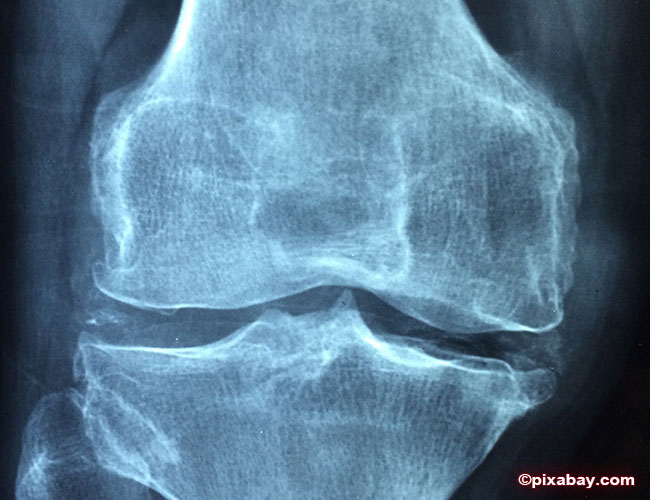

Eine so genannte Schmerztherapie ist eine besondere Therapieform, die gegen zahlreiche schmerzliche Leiden eingesetzt wird. Hauptsächlich kommt sie bei Arthrosen in Hüft-, Schulter- und Kniegelenken zum Einsatz.

Ziel dieser Therapie ist es, den Patienten optimal zu behandeln und schmerzfrei zu machen, damit er wieder aktiv am normalen Alltag teilnehmen kann. Dies ist besonders wichtig, da sich Gelenke leider ähnlich wie das Gehirn verhalten. Nutzt man diese aufgrund der Schmerzen nur selten oder gar nicht, fangen sie an sich zurückzubilden.

Dem kann man durch ständiges „Training“ entgegenwirken und beugt so der durch mangelnde Bewegung verursachten Arthrose vor. Eine seit Jahren bewährte Maßnahme gegen Arthrose, ist die von vielen Medizinern eingesetzte Schmerztherapie. Die Schmerztherapie München setzt hierbei beispielsweise autologes conditioniertes Plasma ein. In betroffene Gelenke werden körpereigene arthrosehemmende Blutbestandteile gespritzt, welche eine direkte Heilung vor Ort fördern. Zur Schmerzvorbeugung und -bekämpfung wird zudem die immer beliebter werdende Hyaluronsäure eingesetzt.